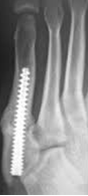

手術療法

骨の転位が強く、骨癒合乏しい場合は手術療法を選択します。

手術方法は①プレート固定、②ピンニング固定、③スクリュー固定